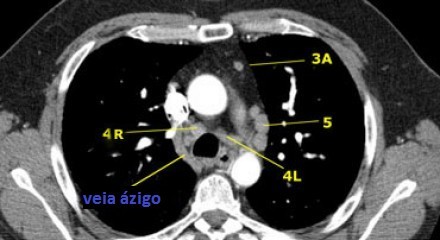

4R. Paratraqueais Inferiores Direitos

Limite superior: intersecção da margem caudal da veia inominada (brachiocefálica esquerda) com a traqueia.

Limite inferior: borda inferior da veia ázigo.

Linfonodos 4R estendem-se para a borda lateral esquerda da traqueia.

5. Linfonodos Subaórticos